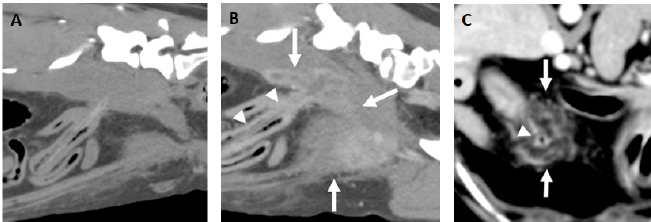

Fig. 1. Examples of fragments of wooden skewer perforating a jejunal loop. A and B. Parasagittal pre (A) and postcontrast (B) images (level 40 HU, width 250 HU) of the same patient with a fragmented wooden skewer (arrowheads) perforating the jejunum in the caudal abdomen with the ending tip penetrating the right psoas muscles. In the pre-contrast images, the portion of the foreign body embedded in the soft tissues is better visualized than in the post-contrast images, while the soft tissue abscessation is better depicted in the latter (arrows). C. Transverse post-contrast CT image (level 40 HU, width 250 HU) of another patient showing a hypoattenuating fragmented wooden skewer foreign body (arrowhead) penetrating a jejunal loop in the cranial abdomen. A marked peritoneal fat stranding is seen surrounding the small bowel loop and foreign body (arrows).

It has been previously speculated that the length and rigidity of this type of wooden foreign bodies prevent them from passing into the body or antrum of the stomach and cause them to perforate the wall of the fundus (Penninck and Mitchell, 2003). Accordingly, all the largest foreign bodies had one of the tips lodged in the stomach and longer perforating trajectories that extended either into the thorax or paravertebral/costal soft tissues depending on the orientation. The remaining and shorter foreign bodies were more prone to advance into distal portions of the gastrointestinal tract causing perforating lesions in the jejunum (Fig. 1). However, one of these smaller wooden foreign bodies was within a right caudal lung lobe and a clear communication with the abdomen was not seen on CT images. An origin from the digestive system, either the oesophagus or the stomach, was suspected as there was no previous history or secondary lesions supporting a theoretical inhalation or penetrating trajectory from the thoracic wall. Interestingly, this patient had a previous history of resolved abdominal effusion which could potentially be explained if a migrating pathway from the gastrointestinal tract was followed by the fragmented wooden skewer.